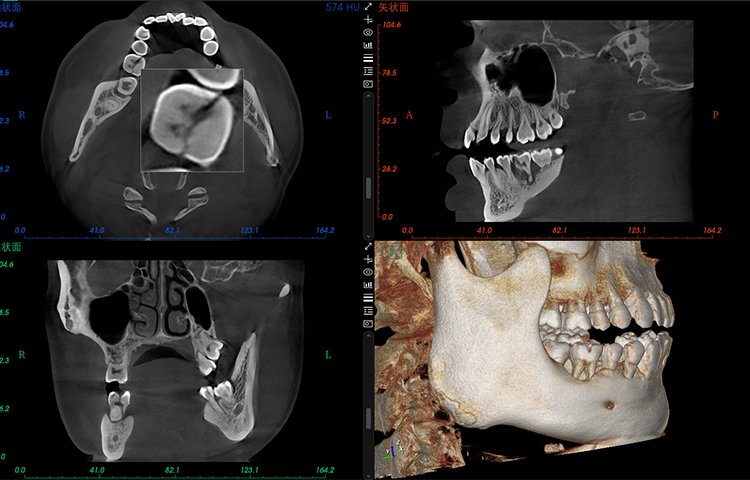

- Amplio campo de visión, satisfaciendo las necesidades clínicas generales.

- Potente funcionalidad, mejorando fácilmente la eficiencia clínica.

Potente Funcionalidad

El software de diagnóstico 3D líder de Meyer y el sistema de análisis ortodóntico inteligente adoptan un diseño de UI modular, lo que hace que las funciones del software sean más cercanas a las necesidades clínicas y más fáciles de usar para los médicos, reduciendo significativamente el costo de aprendizaje.